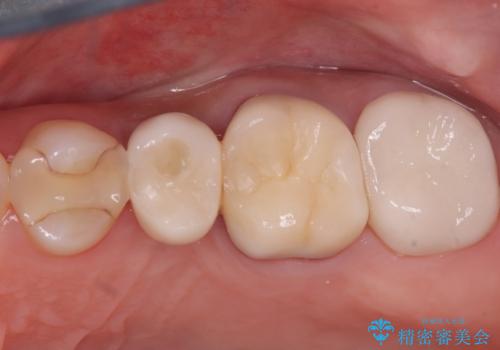

左上第一小臼歯のインプラント治療

待時埋入では、抜歯後に骨の再生を待つ必要があり、即時埋入に比べて治療期間が長くなります。しかし、デンサーバーを使用した精密なドリリングによって、上顎洞粘膜を破らずにインプラントを埋入することができ、術後の合併症リスクを最小限に抑えることができました。インプラント埋入後は、骨との結合を待ちながらしっかりとしたケアと定期的な検診を行い、最終的な補綴物の装着に備えます。